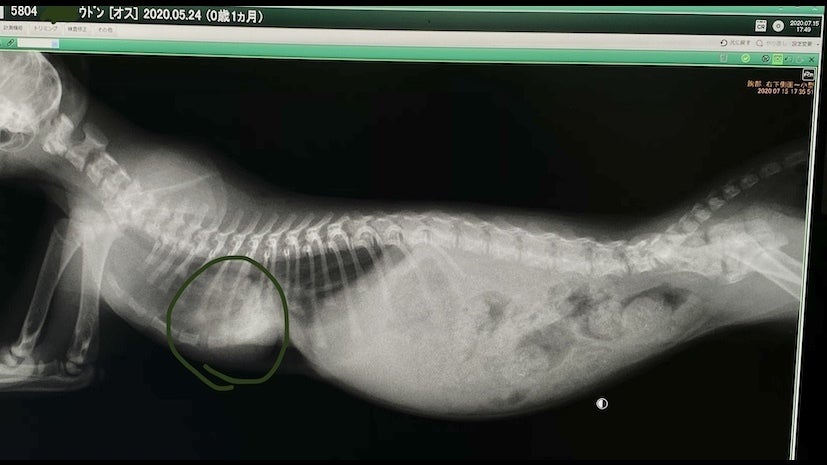

レントゲンを見た感じだと肋骨が内蔵(心臓)にくい込んでいる(通常じゃ有り得ないことなのでまだ未確定)可能性があり手術の難度も上がり、費用も通常よりもかなり高額になるとの事です。

見にくいですが肋骨の下に心臓(緑の丸の部分)があります。

肺も小さいので肺活量がかなり少なく、すぐにバテて動けなくなります…